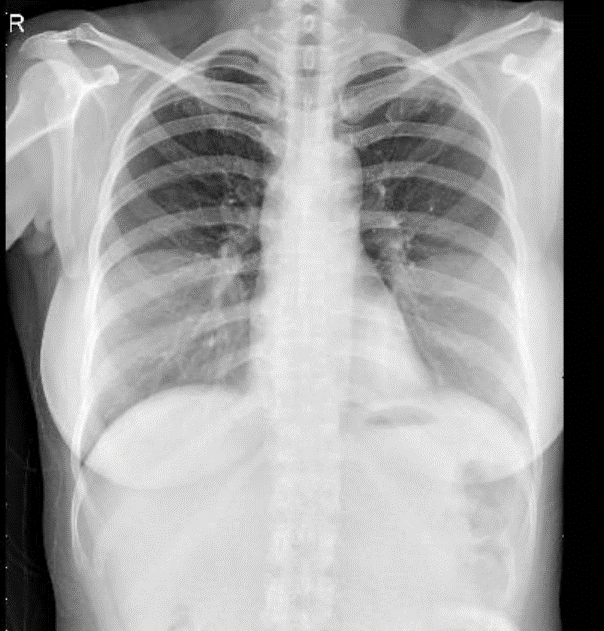

Hãy phân tích tình huống NỮ 45 tuổi -CĐ: Thẩm mỹ

1-Ảnh giả thành ngực hai bên